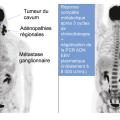

Cancers des voies aérodigestives supérieures : le cas particulier du cancer du nasopharynx

Les carcinomes nasopharyngés (CNP), ou cancers du cavum, sont le plus souvent diagnostiqués devant des signes rhinologiques, auditifs ou neurologiques non spécifiques, conséquences de leur évolution locorégionale ; plus rarement, des signes généraux doivent faire évoquer ce diagnostic, particulièrement si le patient est natif de la…